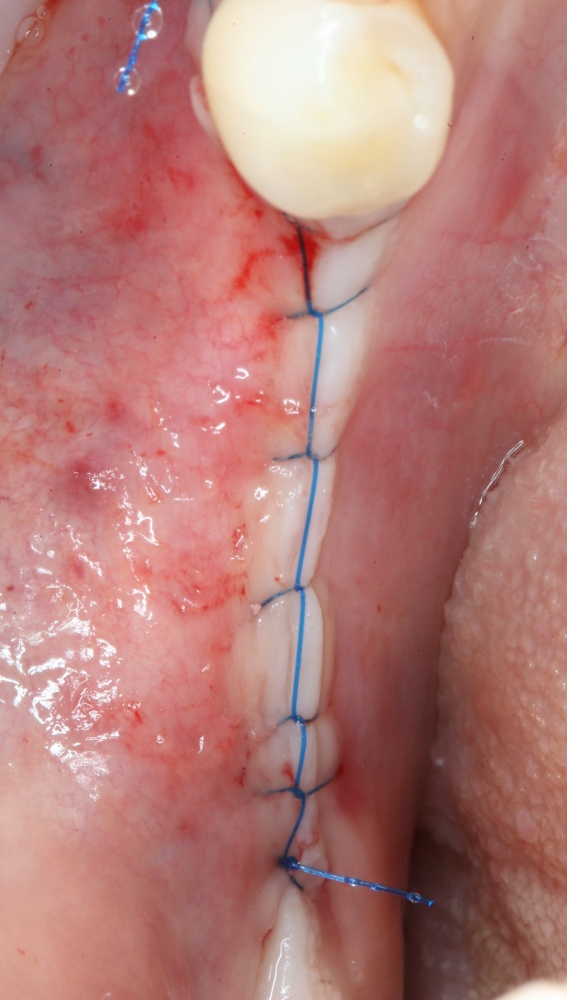

Наложение швов.

Если на этапе разреза и формирования раны всё сделано правильно, то наложение швов не вызывает особых трудностей. Периостотомия или послабляющие разрезы на периосте не требуются (ни практически никогда не требуются). А сами швы получаются аккуратными и герметичными:

Обрати внимание, что все шовные лигатуры находятся в пределах кератинизированной десны. Это позволяет избежать деформации тканей и лишних рубцов. В наиболее уязвимых местах (около зубов) шовные лигатуры лучше продублировать.

Если бы мне пришлось делать это сейчас, то я бы использовал непрерывный «матрацный» шов. Он удобнее, быстрее в наложении и комфортнее для пациента. Минус — если распускается, то распускается весь. К тому же, его очень неудобно снимать.

Несмотря на то, что уже тогда мы широко использовали непрерывные швы в подобных случаях, здесь я, во-первых, зассал (может распуститься), во-вторых, снятие швов предполагалось в поликлинике по месту жительства пациентки, и мне не хотелось, чтобы там при снятии швов начудили. Как выяснится позже — зря беспокоился.

Неизменно одно — в таких операциях мы использовали и до сих пор используем нерезорбируемые монофиламентные шовные материалы, поскольку они наиболее гигиеничные. Чтобы острые концы нитей не беспокоили пациента, их можно оплавить нагретой гладилкой или гуттаперчевым плаггером.